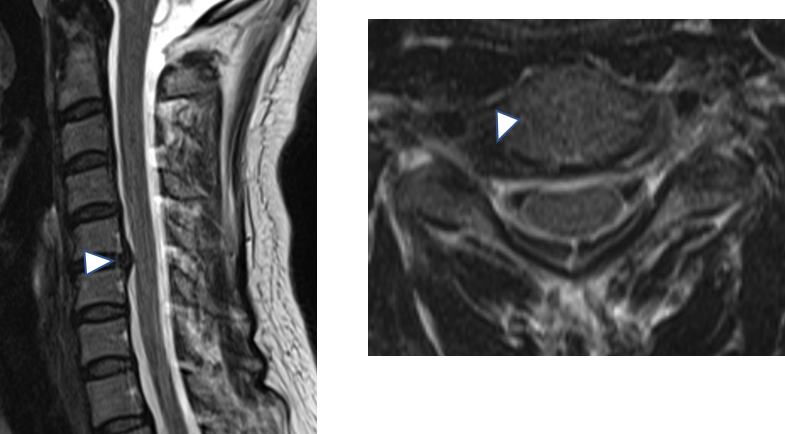

1. 頚椎椎間板ヘルニア

椎間板が突出し神経を圧迫することで、

腕や手のしびれや握力低下が起こることがあります。

軽症であれば保存療法、

症状が重い場合は手術が検討されます。